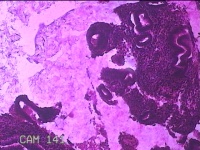

子宫腔赘生物(大)

性别

女

年龄

38岁

临床诊断

子宫内膜息肉;子宫异常出血

一般病史

月经量多数年,发现宫腔占位1个月。

标本名称

大体所见

灰白暗红色不规则肿物2.7x1.8x0.8cm一堆,切开肿物呈实性,切面灰白暗红色,质软。

图2

有那么点像子宫内膜息肉,片子这个效果,辩认起来非常困难。